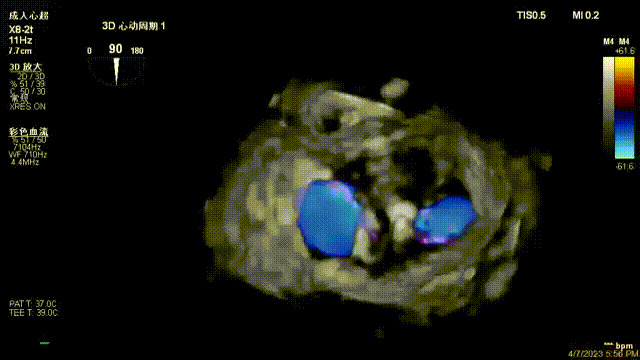

出院前隨訪超聲

接受治療的是一例器質性重度二尖瓣反流(DMR)患者,主訴“反復活動后胸悶,氣促3年余”。術前超聲顯示,雙房增大,二尖瓣脫垂伴重度反流,輕度三尖瓣反流,輕度肺高壓,升主動脈增寬。手術經股靜脈-房間隔入路,采用全身麻醉插管,在TEE和DSA引導下完成房間隔穿刺。置入JensClip瓣膜夾系統后,在左房調整瓣膜夾的位置和軸向,后進入左室,在TEE引導下捕捉二尖瓣前后瓣葉,并關閉瓣膜夾。經TEE反復確認手術效果后最終鎖定并釋放瓣膜夾。術后即刻超聲顯示瓣膜夾位置穩定,功能良好,術前二尖瓣反流4+,術后0反流,肺靜脈逆流和左房壓都顯著好轉,手術圓滿成功(以上數據都來源于醫院的臨床記錄)。術后患者狀態良好,目前已安排出院。